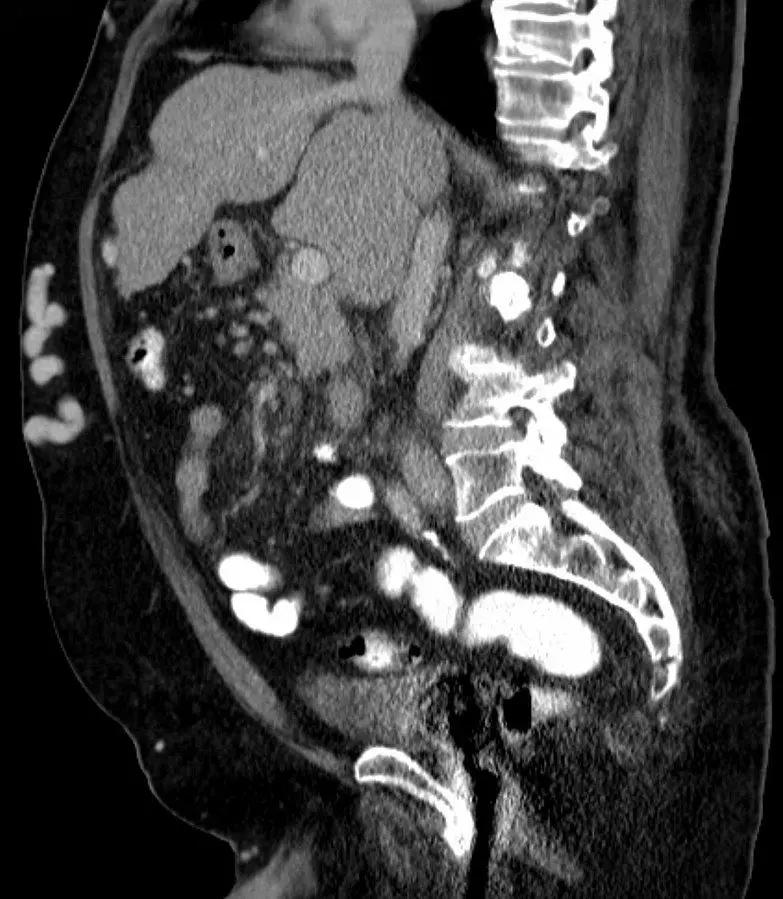

Image - CT scan showing caput medusa. Look for the collection of fluid that is most superficial on the abdomen (fluid is white on CT scan)

Creative commons source by Hellerhoff [CC BY-SA 4.0 (https://creativecommons.org/licenses/by-sa/4.0)]